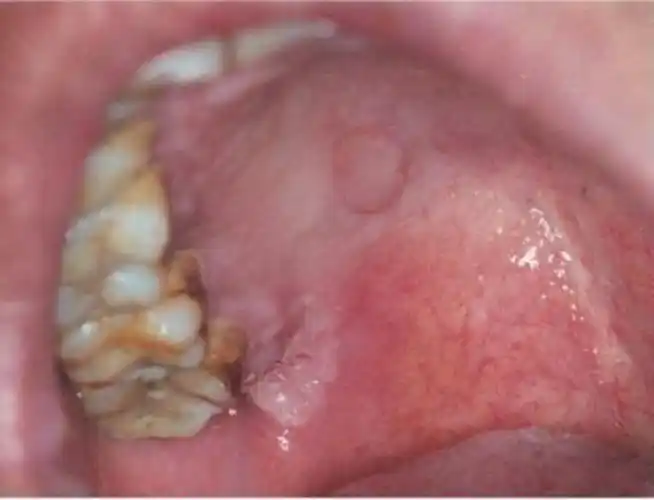

梅毒疹是感染梅毒后所表现出的二期梅毒临床症状之一,可分为斑疹性

梅毒二期症状 (13)

梅毒疹图片_梅毒疹图片和症状图片